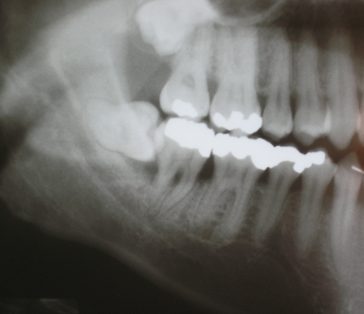

- שיקולים אנטומיים – שיניים עם שורשים מעוותים או שבורים עשויות לדרוש עקירה כירורגית כדי להבטיח שכל חלקי השן יוסרו.

- שיניים שבורות או עששת עמוקה – שיניים שנפגעו קשות או בעלות עששת עמוקה עשויות להיות מאתגרות לחילוץ באמצעות עקירה רגילה.

- שורשים מפוצלים – שיניים עם שורשים מפוצלים זקוקות לרוב להתערבות כירורגית כדי להבטיח הסרה מלאה.

- מיקום השיניים – שיניים הממוקמות בזוויות קשות עשויות לדרוש עקירה כירורגית.